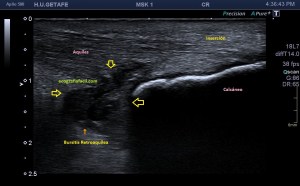

Si observamos la bursitis retroaquílea de la imagen 11(flechas amarillas), además la exóstosis de la imagen 13 y deformidad en la piel, observable sin ecografía podemos estar ante un síndrome de Haglund de esos de libro…y tendremos una imagen ecográfica como la de la imagen 14.

Como has visto en la imagen 1, la bursa retroaquílea no debe verse, ese receso debe tener como mucho una mínima cantidad de líquido, que como digo es normal, pero no lo que observamos en la imagen 11 donde vemos una imagen heterogénea ocupando esa región.

Corrobora si el paciente tiene estudios radiológicos simples que estén en concordancia con la imagen 10, por ejemplo, la imagen 12.

La flecha amarilla indica la que en la parte posterior del calcáneo existe un calcio tosco en esta rx lateral del pie en carga, pero es en la inserción, cuidado con esto, cuando se produce el Haglund, no es en la inserción, es antes, y se debe a la exostosis mencionada con anterioridad, mira, compara imagen 12 e imagen 13. La flecha roja es indicativa de Síndrome de Haglund.

13

14

En la imagen 14, como no podía ser de otra manera, observamos todo y es por definición la típica imagen de S.Haglund.